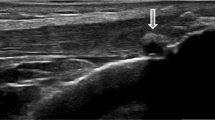

Although the best imaging method to investigate the presence of MSU crystal deposits in the early stages has not yet been established [5], ultrasound (US) has been demonstrated to be a valid imaging modality to detect musculoskeletal involvement in patients with gout [6–9]. The main US findings related to MSU crystal deposition include hyperechoic enhancement of the superficial margin of the hyaline cartilage (double contour sign), hyperechoic spots within tendons and soft tissues, tophi and bone erosions [7, 10, 11]. Additionally, an increase of blood flow surrounding the MSU deposits detected by power Doppler (PD) has been described as an indicator of inflammatory activity [5, 7].

On femoral hyaline cartilage, the double contour sign (Figure 1A) was present in 17 of 100 knees from hyperuricemic patients in contrast to none in the control group (P < 0.0001), giving an odds ratio (OR) of 43.8 (95% confidence interval (95% CI), 2.9 to 739). The prevalence of the double contour sign in the first MTPJs (Figure 1B) was also higher in hyperuricemic patients (25% vs. 0%; P < 0.0001), with an OR of 34.3 (95% CI, 4.5 to 259). However, no correlation between SU concentration and the presence of the double contour sign was found (rs -0.06; 95% CI, -0.3 to 0.2).

Chronically elevated SU has not usually been considered to play a pathogenic role in tissue damage. However, large prospective population studies are challenging this notion, since they have found that SU levels are reliable and consistent predictors of progression for endothelial dysfunction [16], coronary artery disease [17, 18] and renal failure [2]. In this line of thought, our results support the existence of both intra- and extra-articular tissue damage caused by the persistent elevation of SU [5]. The presence of MSU crystals in the synovial fluid from asymptomatic individuals with hyperuricemia has been demonstrated on the basis of polarized light microscopy since the early 1980s [4]. In accord with this evidence, the double contour sign has been described solely in gout and seems to represent the preference of SU to crystallize on the surface of cartilage [7, 11, 19]. Even when the underlying mechanisms for this preference need further clarification, it has been shown that the normal components of cartilage chondroitin sulfate and phosphatidylcholine facilitate the nucleation and subsequent crystallization of MSU [20]. As confirmation of the presence of MSU in the hyaline cartilage, Thiele and Schlesinger [21] recently demonstrated the disappearance of the double contour sign in patients with gout successfully treated with urate-lowering agents who had maintained SU levels below 6 mg/dL for at least 7 months. Also, tophi formation detected in our study further confirmed the presence of MSU crystal tissue deposition in both intra- and extra-articular structures from asymptomatic hyperuricemic individuals as previously suggested [5]. This may strengthen the need for treatment necessity in asymptomatic individuals with hyperuricemia and indisputable US features of MSU crystal tissue deposition such as the double contour sign or the presence of tophi [3].

Recently, US has been shown to be of value in revealing subclinical joint and tendon inflammation in patients with other inflammatory conditions such as arthritis [22, 23], psoriasis [24] and Sjögren's syndrome [25]. This prompted us to investigate its ability to identify the involvement of the hyaline cartilage, tendons and joints in individuals with asymptomatic hyperuricemia and no signs of inflammation or musculoskeletal complaints. Our results are in agreement with a previous report [5]. Indeed, Puig et al. [5] studied 35 asymptomatic individuals with hyperuricemia and found tophi formation in both tendons and synovium in 34% of patients, with a special preference for the distal patellar tendon. Here we have extended the US evaluation to other anatomical sites characteristically involved in gout, such as the hyaline cartilage and first MTPJs, and have shown that MSU crystal deposition and structural damage in these locations may be even greater and more frequent than in tendons. Additionally, the present study was carried out in a higher number of participants and included a normouricemic, healthy control group. Further differences between studies are related to our findings of bone erosion and synovial fluid and/or hypertrophy, both of which are common features of gout but were not assessed in the study by Puig et al. [5].